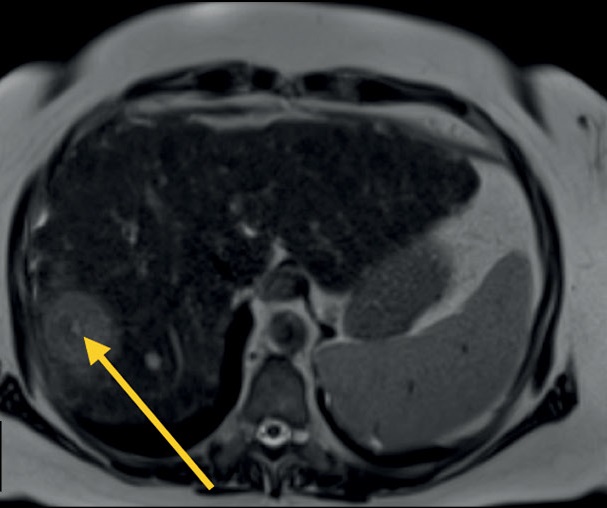

磁共振成像是诊断腹部和腹膜后器官疾病的主要方法之一,它允许显示出实质器官和空腔脏器的病灶或弥漫性变化,具有很高的诊断准确度和可重复性。与计算机断层扫描相比,磁共振成像在确定实质器官、胆道和胰管、腹膜和腹膜后器官的病理变化的敏感性和特异性方面有明显优势。

多参数扫描方案不仅提供器官的相互形貌及其结构的信息,而且提供组织的功能状态,使图像从结构评估过渡到功能评估。在大多数情况下,标准方案包括腹部扫描(T1-/T2-和扩散加权模式)和胆道扫描(磁共振胆胰管成象),但根据检查的目的和病人的情况,这个方案可以大大缩短或补充。